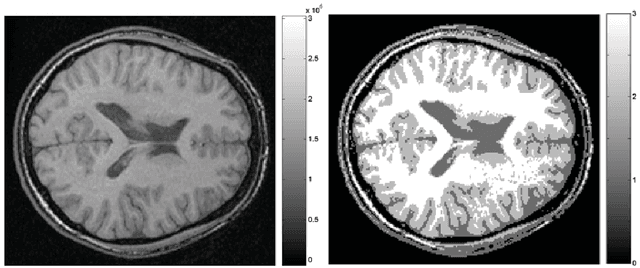

This article is based on the first chapter of book Chung (2013), where brain and medical images are introduced. The most widely used brain imaging modalities are magnetic resonance images (MRI), functional-MRI (fMRI) and diffusion tensor images (DTI). A brief introduction to each imaging modality is explained. Further, we explain what kind of curve, volume and surface data that can be extracted from each modality.